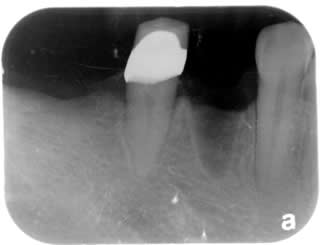

3 Implants:

Feb 2009

Going to wait four months after the implants are placed before the crowns can be placed.